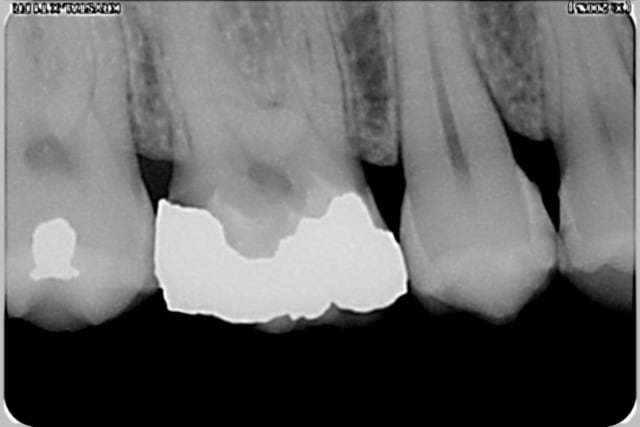

et deux exemples en radios de cas similaires, un peu plus sous gingivaux d'ailleurs

Post op 2 copy js6kde - Eugenol

Pr  op 3 copy pifnpq - Eugenol